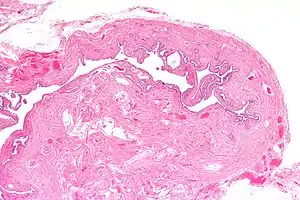

| Micrograph of salpingitis isthmica nodosa, showing the characteristic nodular thickening. H&E stain. | |

It is characterized by nodular thickening of the tunica muscularis of the narrow (isthmic) portion of the Fallopian tube. In severe cases, it leads to complete obliteration of the tubal lumen. It is uncommonly bilateral.[2]

Microscopic Findings:

- Glandular epithelium within tubal muscularis propria, in continuation with mucosa or (more commonly) discontinuous

- Haphazard distribution (akin to adenomyosis) or pseudoinfiltrative

- Banal epithelium with tubal differentiation[4]